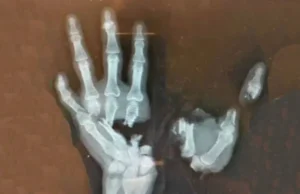

Ovako izgleda šaka dječaka koju je uništila eksplozija petarde

Na fotografiji je rentgenski snimak šake dečaka (12) koji je teško povređen prilikom eksplozije petarde u ruci. Eksplozija u njegovoj ruci uništila je šaku,...